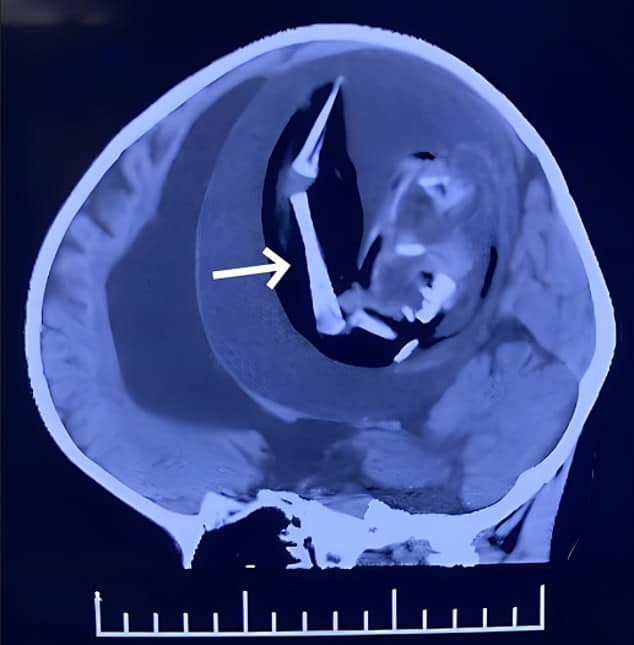

แพทย์จึงสแกนศีรษะของเด็ก พบก้อนเนื้อขนาดเส้นผ่านศูนย์กลาง 13 เซนติเมตรในกะโหลกศีรษะ ซึ่งมีขนาดใหญ่กว่าลูกเบสบอลเล็กน้อย ภายในก้อนเนื้อมีชิ้นส่วนของกระดูกยาวฝังอยู่